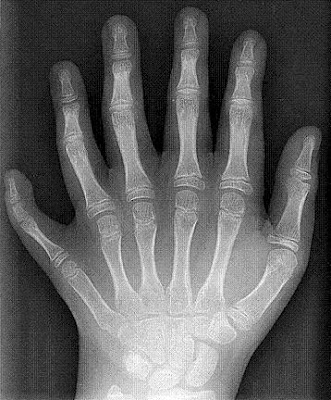

2. Pemain bisbol dengan 12 jari

Antonio Anfonseca, seorang pitcher bisbol liga utama memiliki enam jari pada setiap tangannya. Kondisi ini disebut dengan polydactylism (adanya kelebihan jari tangan atau kaki) yang terkadang bisa menghambat mobilitas seseorang. Diperkirakan satu dari 500 anak mengalami kondisi ini.